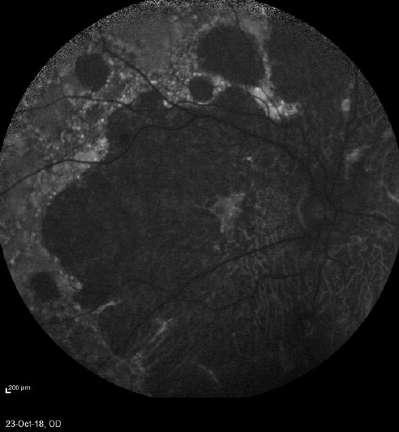

3.B. MELANOMA AMELANÓTICO

Caso aportado por Dr. Osvaldo Weisse

ü Imagen C: Lesión sólida ligeramente irregular, homogénea, de reflectividad media baja con elementos de vascularidad en su interfase. Altamente consistente con melanoma de coroides

ü Mujer 57 años consultó en policlínico por cuadro de disminución de la agudeza visual de hemicampo superior del ojo derecho, indoloro de 1 mes de evolución

ü Imagen B: Subyacente al DR hay una lesion sólida dependiente de la coroides, irregular en base (18.8mm) y altura (1.63)

C

A B

ü Imagen D y E: Lesión coroidea que levanta la macula, asociada a líquido subretinal